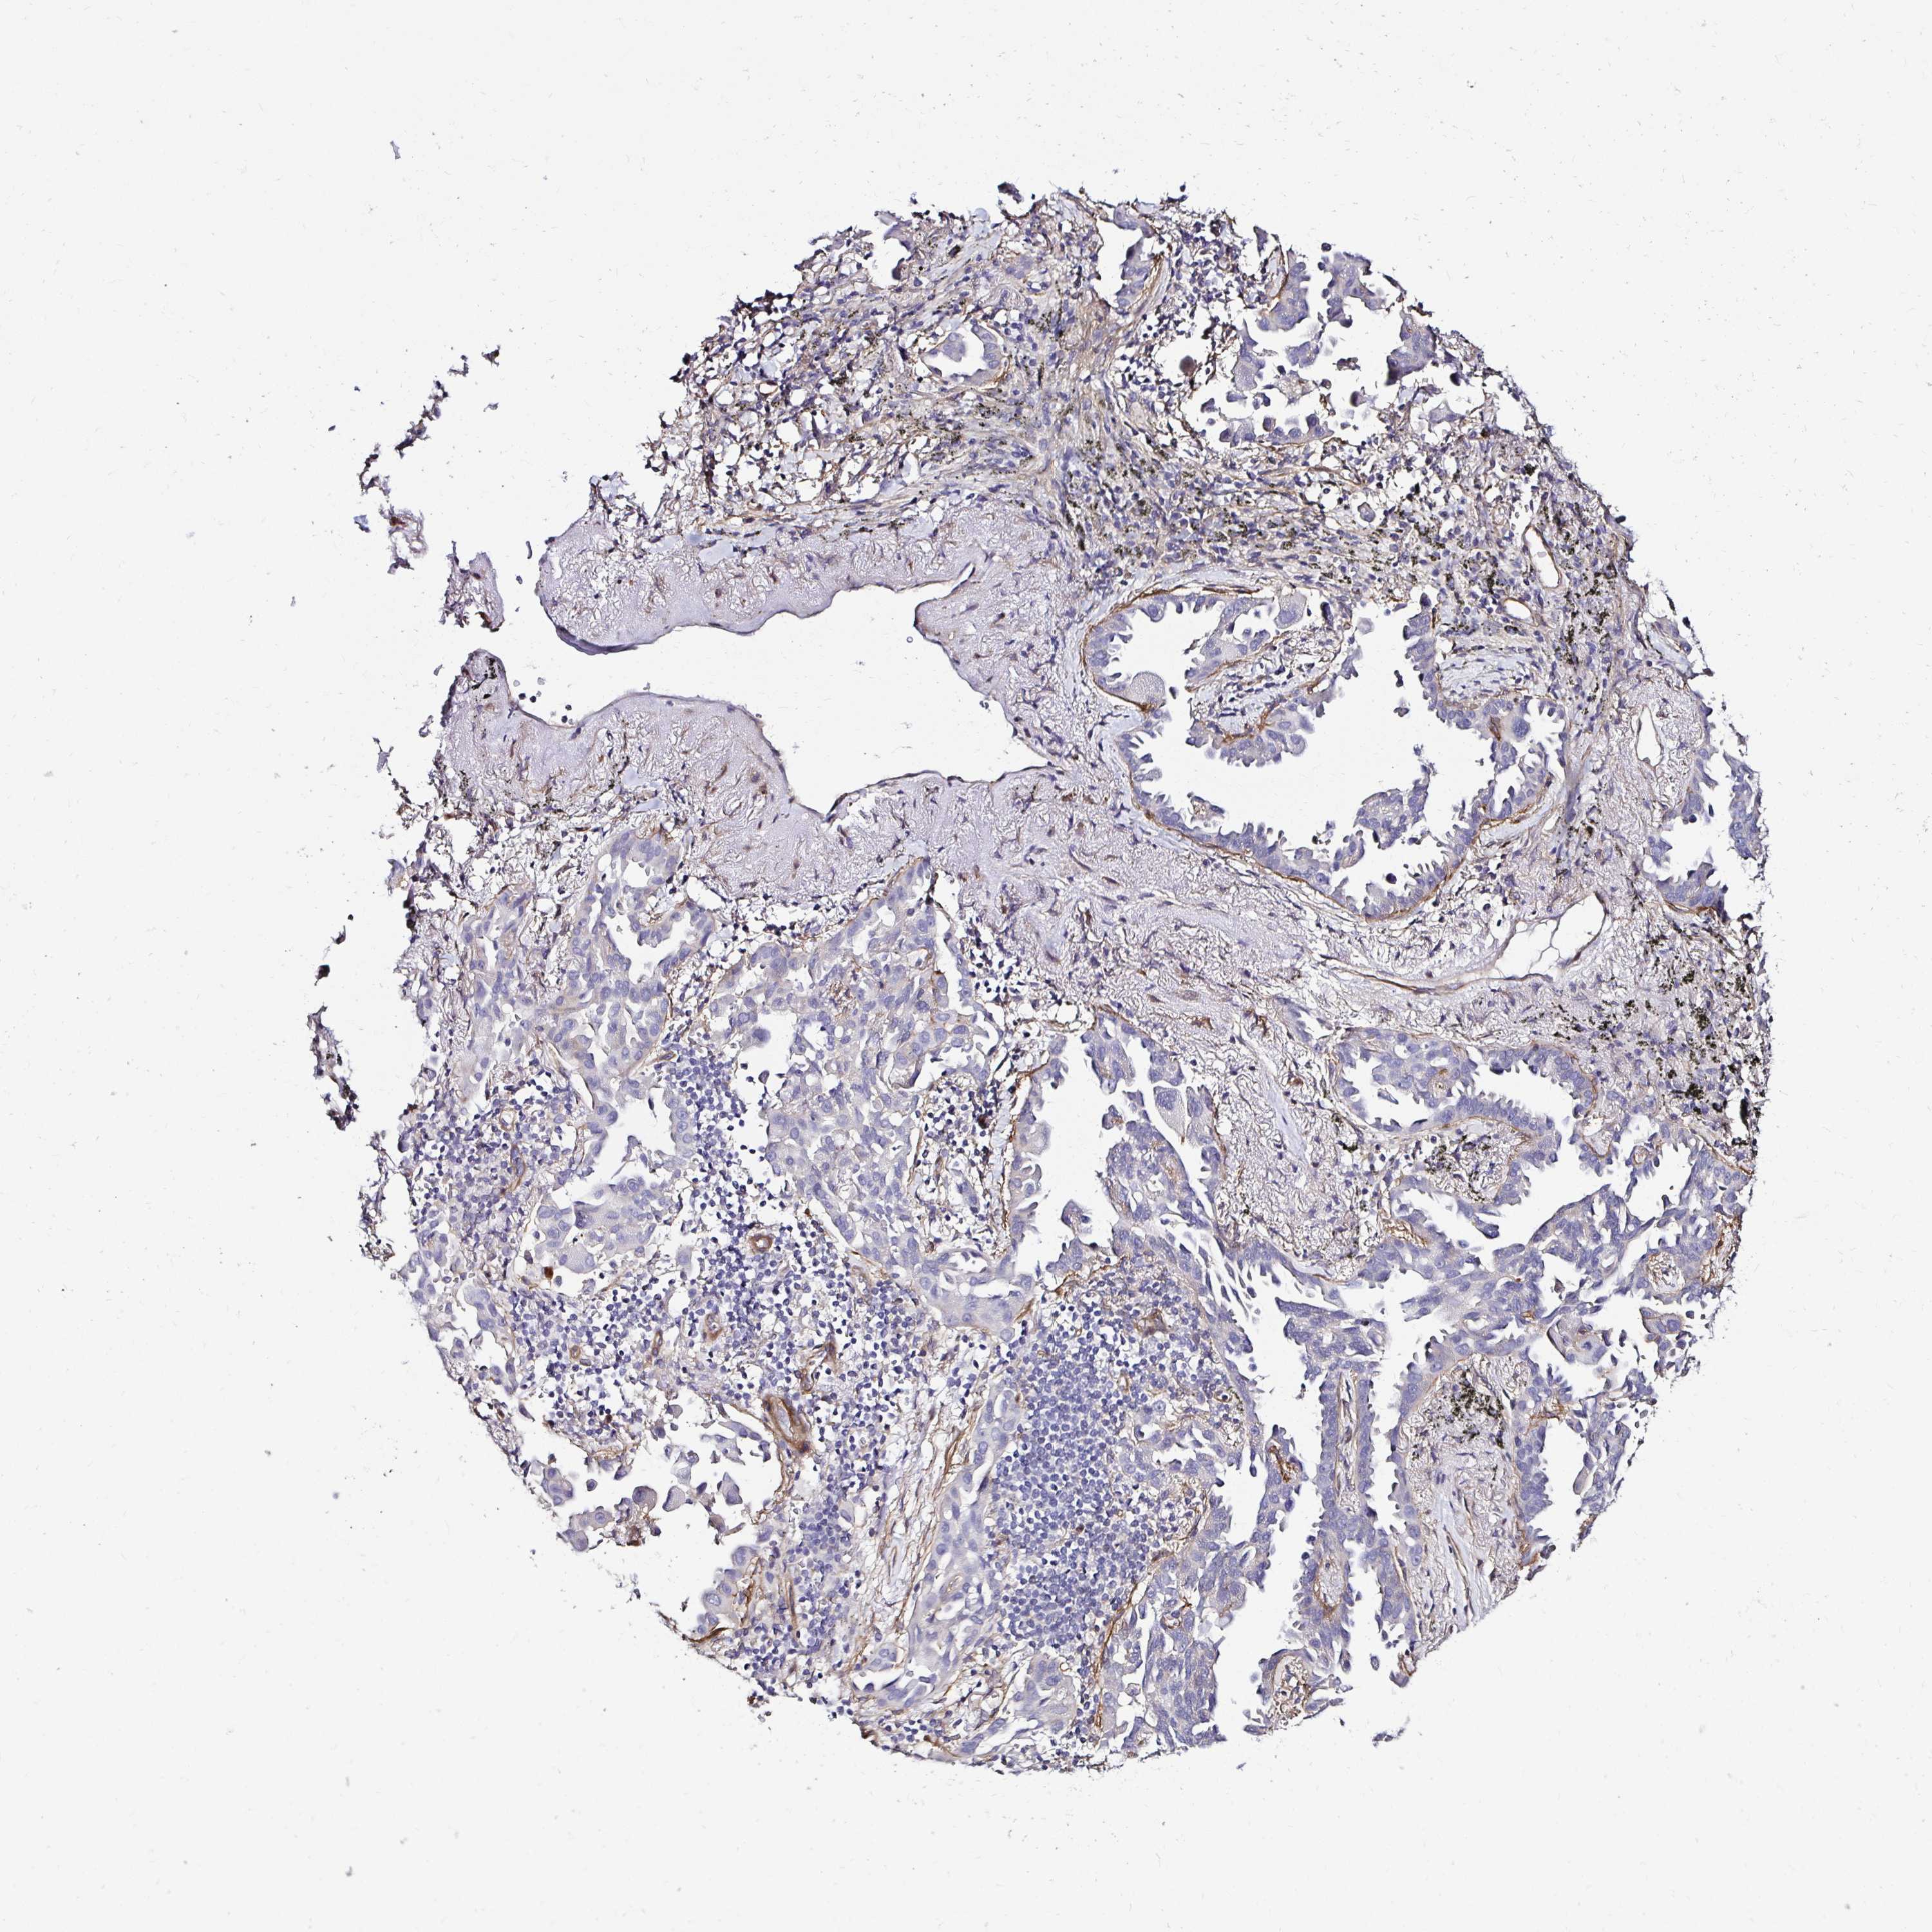

LUNG SQUAMOUS CELL CARCINOMA (TCGA) - Interactive survival scatter ploti

The Survival Scatter plot shows the clinical status (i.e. dead or alive) for all individuals in the patient cohort, based on the same data that underlies the corresponding Kaplan-Meier plots. Patients that are alive at last time for follow-up are shown in blue and patients who have died during the study are shown in red.

The x-axis shows the expression levels (FPKM) of the investigated gene in the tumor tissue at the time of diagnosis. The y-axis shows the follow-up time after diagnosis (years). Both axes are complimented with kernel density curves demonstrating the data density over the axes. The top density plot shows the expression levels (FPKM) distribution among dead (red) and alive patients (blue). The right density plot shows the data density of the survived years of dead patients with high and low expression levels respectively, stratified using the cutoff indicated by the vertical dashed line through the Survival Scatter plot. This cutoff is automatically defined based on the FPKM cutoff that minimizes the p-score. The cutoff can be changed by dragging the vertical line or by entering a cutoff value in the square labeled "Current cut-off".

Under the Survival Scatter plot the p-score landscape (black curve; left axis) is shown together with dead median separation (red curve; right axis). Dead median separation is the difference in median mRNA expression between patients who have died with high and low expression, respectively. It is calculated as follows: median FPKM expression of dead patients with high expression - median FPKM expression of dead patients with low expression. This is intended to aid the user in visually exploring custom cutoffs and the associated p-scores and dead median separation.

Individual patient data is displayed and can be filtered by clicking on one or more of the category buttons on the top of the page. Categories describing expression level and patient information include: high, low, alive, dead, female, male and tumor stages. The scale of the x-axis can be toggled between linear and log-scale by clicking on the "x log" button. Mouse-over function shows TCGA ID, patient information and mRNA expression (FPKM) for each patient.

& Survival analysisi

Kaplan-Meier plots summarize results from analysis of correlation between mRNA expression level and patient survival. Patients were divided based on level of expression into one of the two groups "low" (under cut off) or "high" (over cut off). X-axis shows time for survival (years) and y-axis shows the probability of survival, where 1.0 corresponds to 100 percent.

ITGB1 is potential prognostic, high expression is unfavorable in Lung Squamous Cell Carcinoma (TCGA)

Best expression cut offi

Based on the FPKM value of each gene, patients were classified into two groups and association between prognosis (survival) and gene expression (FPKM) was examined. The best expression cut-off refers the FPKM value that yields maximal difference with regard to survival between the two groups at the lowest log-rank P-value. Best expression cut-off was selected based on survival analysis .

When clicking on this number, the vertical dashed line indicating cut-off, the interactive survival plot, and the Kaplan-Meier curve will be adjusted to show results based on the best expression cut-off.

: 243.57